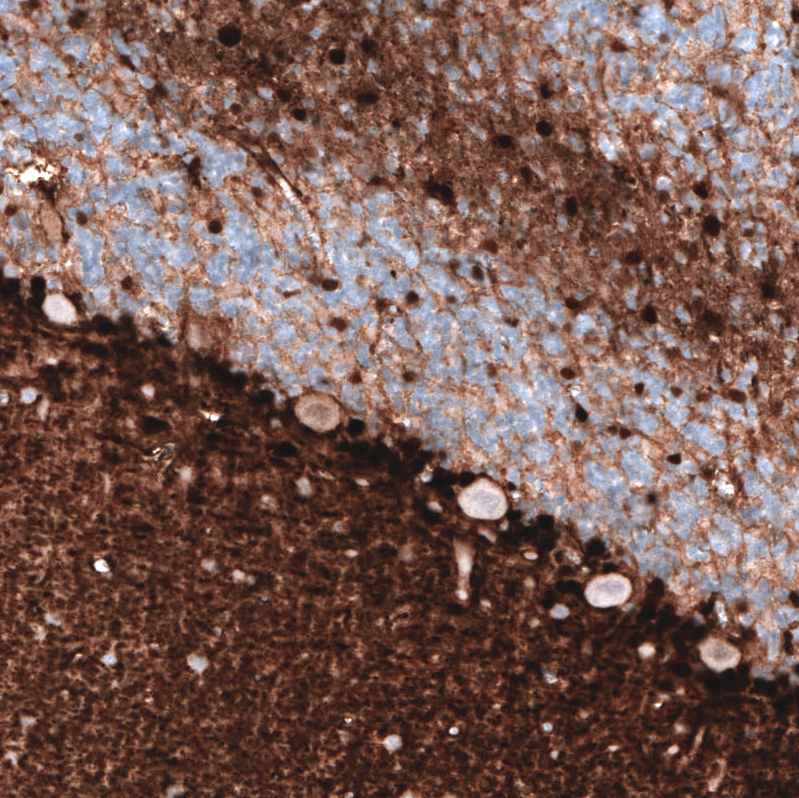

Immunohistochemistry analysis in human cerebral cortex and kidney tissues using AMAb91038 antibody. Corresponding S100B RNA-seq data are presented for the same tissues.